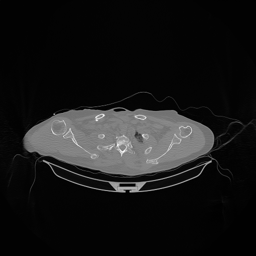

III-D Real Clinical Data Experiment

The experimental results on clinical head data are shown in Fig. 4. The reference images were reconstructed using the fast iterative shrinkage-thresholding algorithm (FISTA) with total variation regularization from non-truncated projection data. In the WCE reconstructions (Fig. 4(b)), severe truncation prevents accurate recovery of anatomical structures outside the FOV. Despite being trained solely on simulated data with a domain gap, all deep learning models can restore a substantial portion of the missing anatomy. Among them, the diffusion-based methods recover soft-tissue boundaries more faithfully than the conventional deep learning approach FBPConvNet, highlighting their stronger image generation capability. However, cDDPM reconstructions exhibit more noticeable noise than those from other methods, consistent with the simulated data results. The patchDiffusion model introduces artifacts within the FOV, likely due to its patch-wise processing strategy. While I2SB shares the same limitations as other diffusion models in perfectly restoring soft-tissue detail, it produces fewer residual noise patterns and fewer artifacts within the FOV boundaries. Overall, Fig. 4 demonstrates the strong efficacy of I2SB in reconstructing real CBCT data.